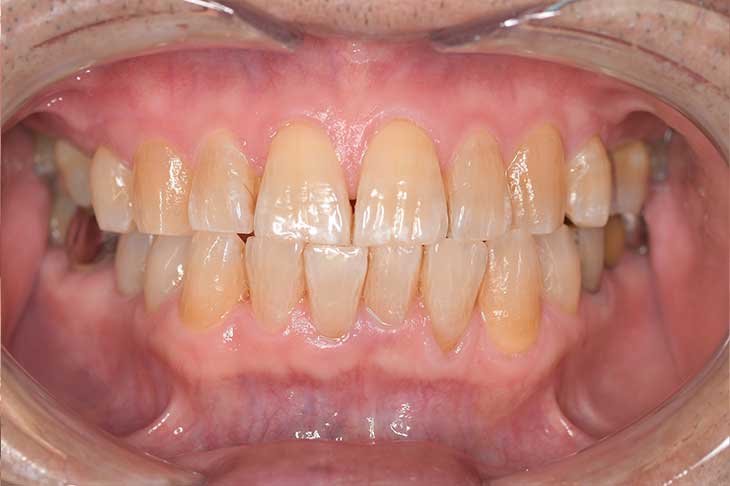

現在の治療費と異なる場合がございます。最新の治療費は料金表をご確認ください。CASE 1

Before

After

基本情報

| 主訴 | 見た目をきれいにしたい |

| 治療期間 | 6ヶ月 |

| 治療費 | ジルコニアボンド(セラミックの被せもの)¥165,000×7(税込み) オフィスホワイトニング4回 ¥4,400×4(税込み) ホームホワイトニング¥11,000 |

| リスク・副作用 | かみ合わせがとても強い方の場合、稀に割れてしまうことがあります。 |

| 先生からの提案 | 上の前歯6本と右下の2番目の歯はセラミックの被せもので治療。 残りの下の前歯5本はプラスチックの材料で虫歯を治療し、 ホワイトニングをおこないました。白くなったご自身の歯の色に合わせてセラミックの 被せものを作成しています。 模型上で完成後をシュミレーションし、上の歯茎の位置をきれいに見えるように 揃えています。(外科処置はしていません) |